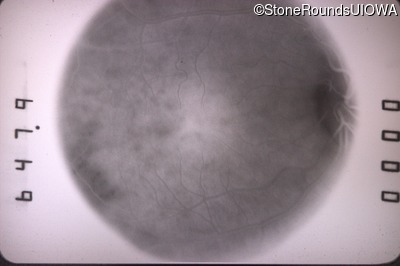

Fundus Photography - Right - 20/40 -2

Exemplar

Fundus Photography - Left - 20/400